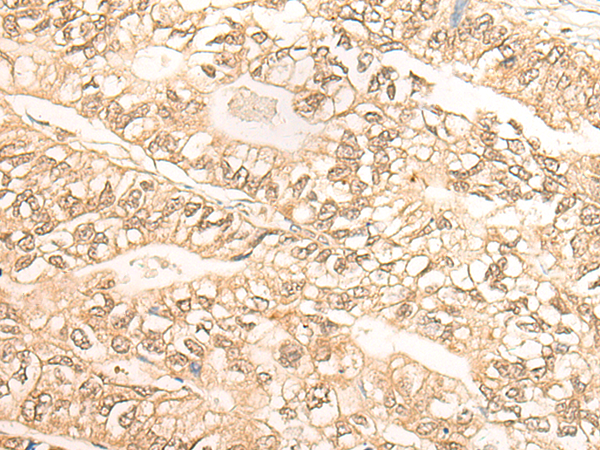

IHC Positive control: |

Human gastric cancer;Human lung cancer |

IHC Recommended dilution: |

30-150 |